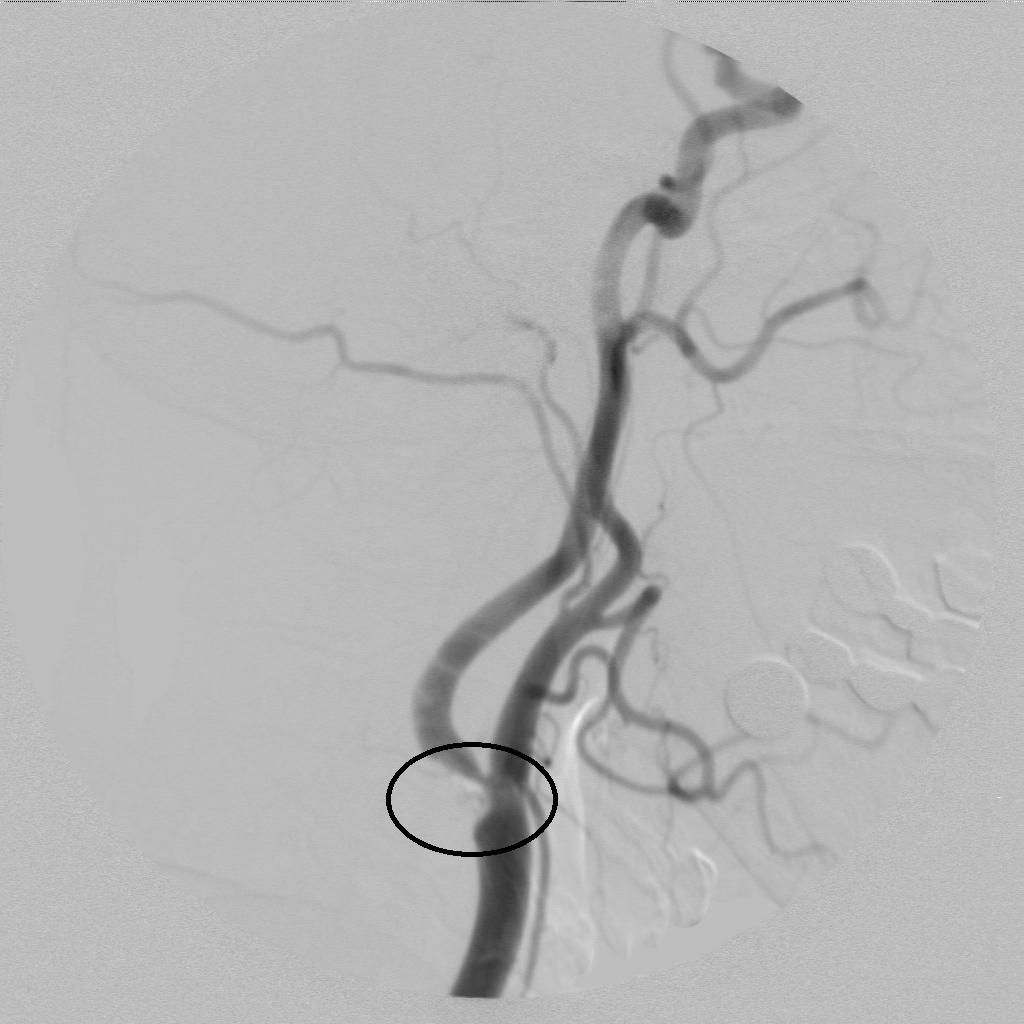

脑血管造影术发现右侧颈内动脉起始部狭窄!